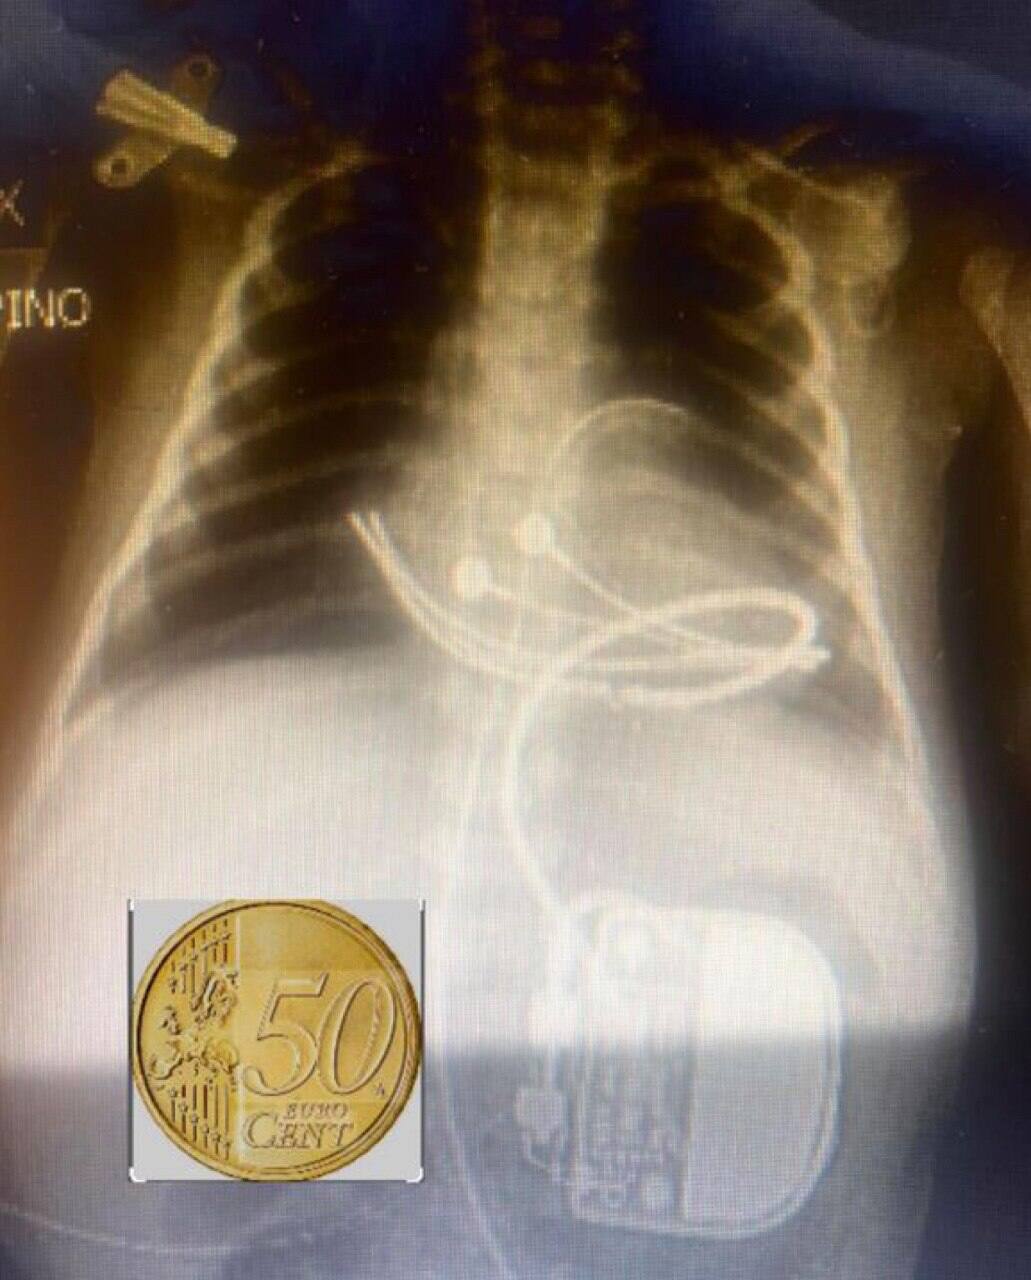

La procedura chirurgica è avvenuta senza complicanze utilizzando uno dei pacemaker più piccoli disponibili (Microny, Abbott, Usa), poco più grande di una moneta da 50 centesimi. Oggi la bambina pesa 2,7 kg e ha ripreso un'alimentazione regolare

La procedura chirurgica è avvenuta senza complicanze utilizzando uno dei pacemaker più piccoli disponibili (Microny, Abbott, Usa), poco più grande di una moneta da 50 centesimi. Gli interventi eseguiti hanno visto coinvolte l'Uoc di anestesia e rianimazione generale diretta da Giacomo Filoni e l'Uoc di anestesia e rianimazione post-cardiochirurgica diretta da Enrico Iannace. "Questo intervento rappresenta un grandissimo esempio di approccio multidisciplinare alle cardiopatie congenite. Oggi la bambina pesa 2,7 kg e ha ripreso un'alimentazione regolare. Il ritorno della madre e della piccola a casa  rappresenta un grande successo frutto di abnegazione e competenze maturate negli anni", dice Sasha Agati, direttore del Ccpm Bambino Gesù di Taormina.